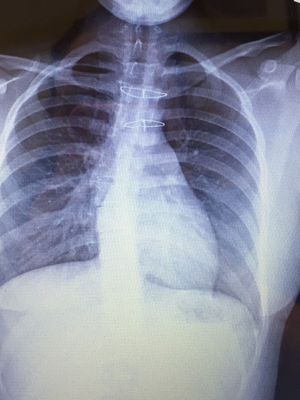

2 sternal wires placed after chest was cracked to fix aorta

Xray

Chest

Wire